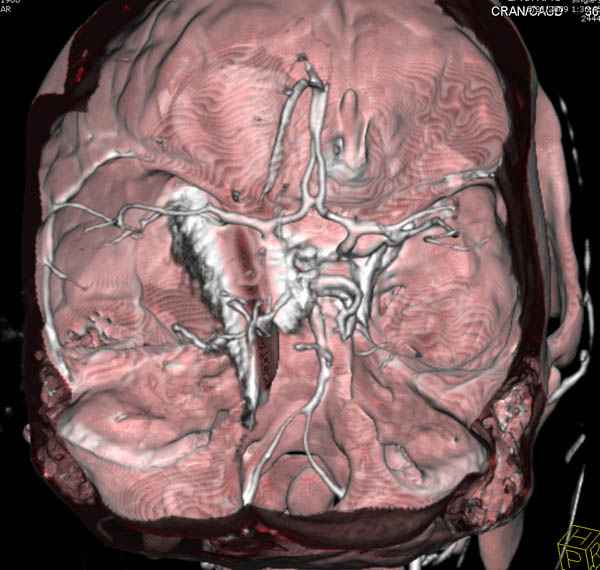

По протоколу сделаны все необходимые исследования: рентген, ангиограмма с 3Д реконструкцией, где обнаружили что все жизненно важные сосуды не задеты, даже некоторые "сидят" изгибаясь на ноже.